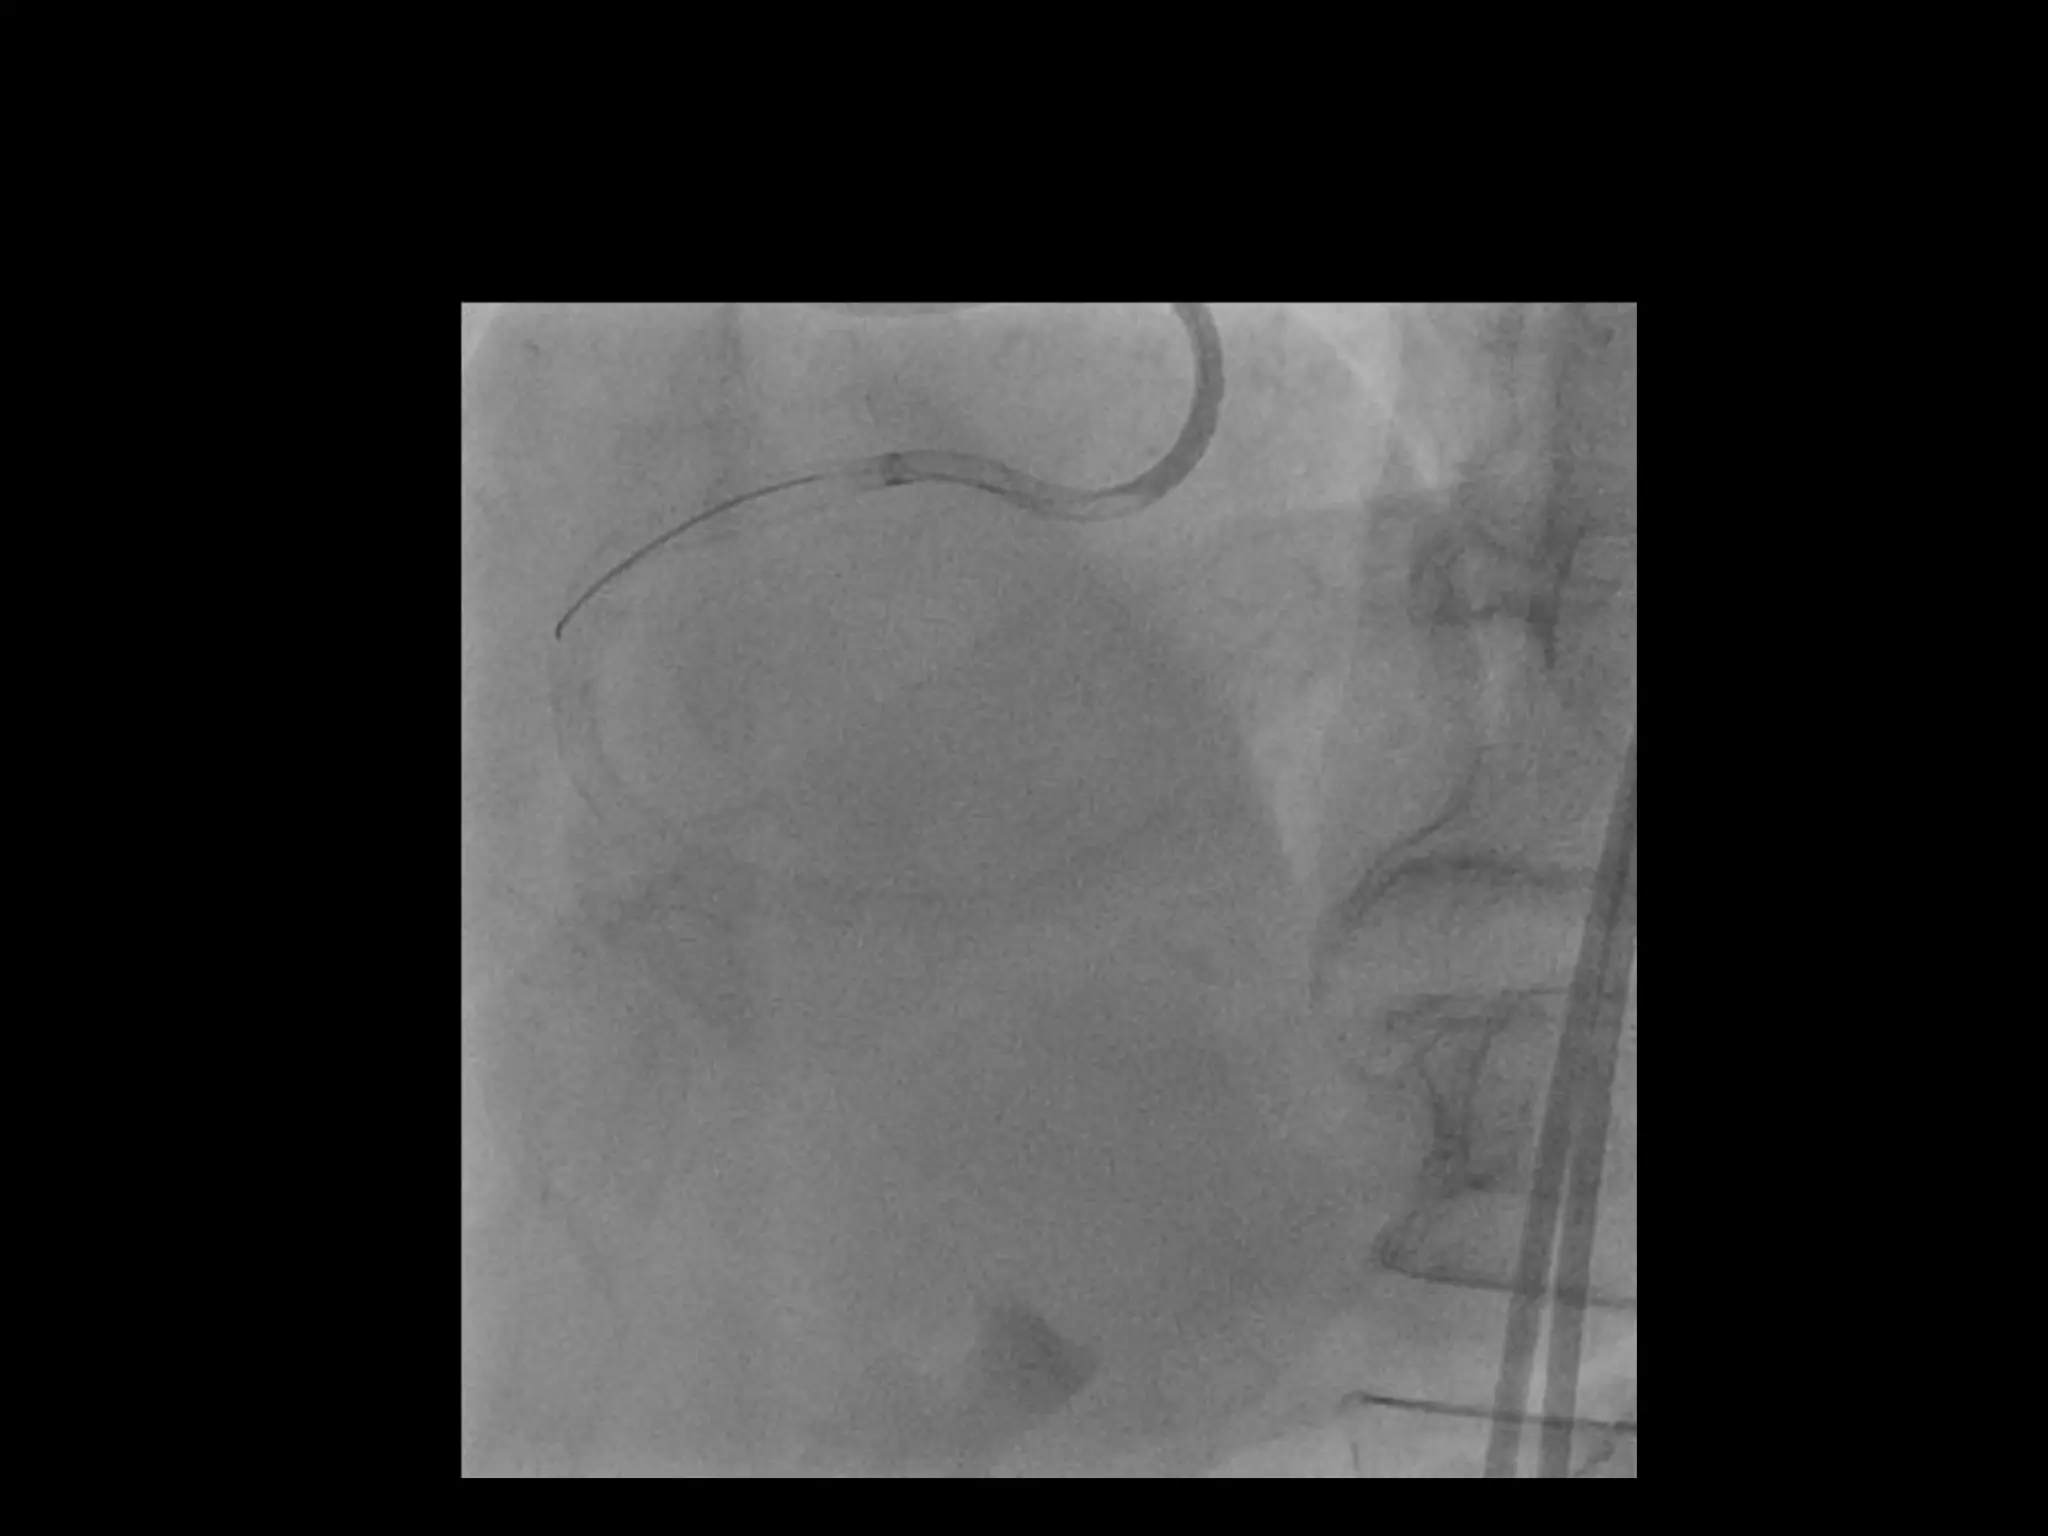

This document provides guidance on evaluating the feasibility of percutaneous coronary intervention (PCI) for a chronic total occlusion (CTO). Key factors to consider include: the patient's tolerance for a long procedure, contrast load, and radiation exposure; the CTO's proximal cap ambiguity, length, distal landing zone, and presence of interventional collaterals; and ensuring good quality angiography. With adequate planning and use of appropriate CTO techniques, feasibility is nearly always present for symptomatic patients. Success rates of CTO-PCI are reported to be 94% when using a planned approach.